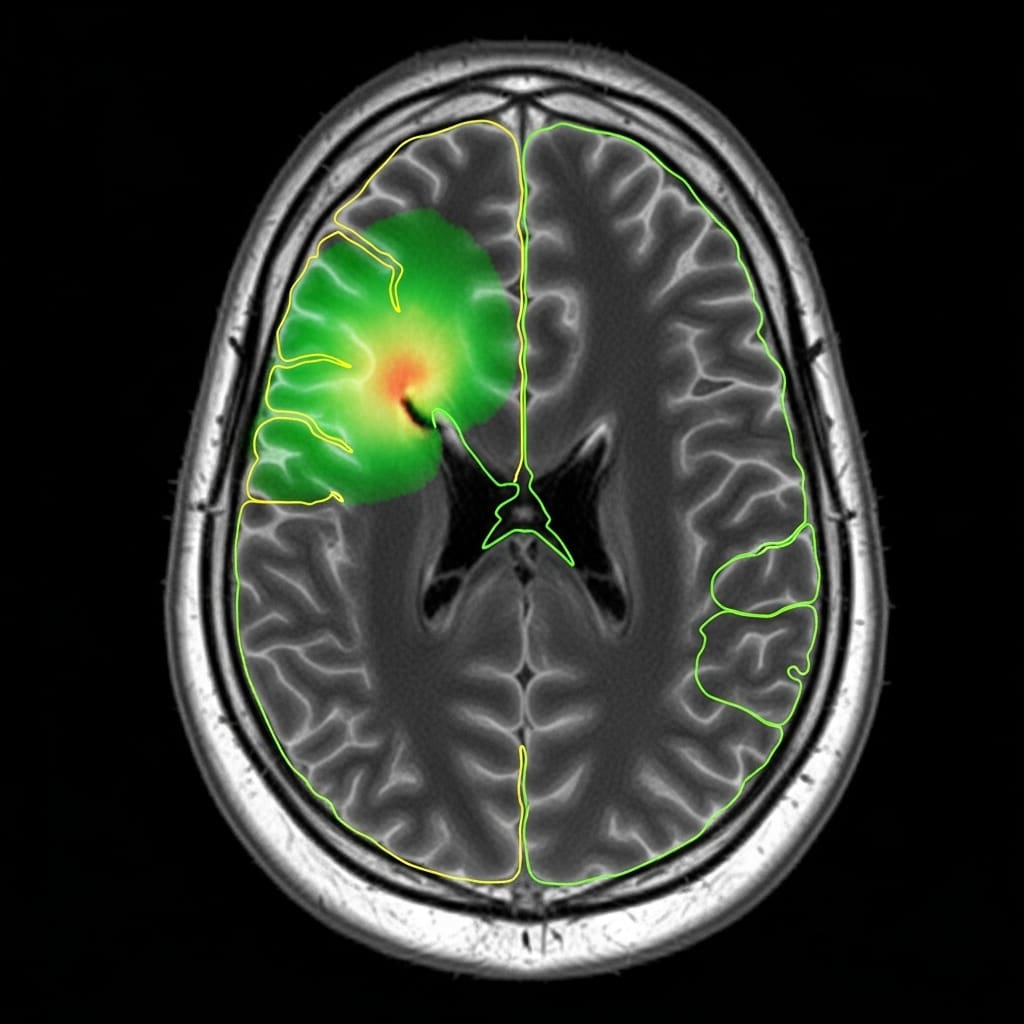

Scientists have demonstrated a significant advancement in brain tumor segmentation, achieving state-of-the-art performance with dramatically reduced computational demands. The research team addressed the challenge of requiring extensive datasets and powerful computing resources, limitations that hinder accessibility for many, by implementing a novel approach based on the Karhunen, Loève Expansion (KLE). This breakthrough enables accurate glioma MRI segmentation using a consumer-grade workstation, opening possibilities for wider clinical adoption and research accessibility. Each 240x240x155 multi-modal MRI scan undergoes downsampling and z-score normalization before being processed by the KLE, reducing it to just 32 KL coefficients and compressing the data into four channels.

The core innovation lies in the creation of a residual-based anomaly map derived from the approximate reconstruction facilitated by the KLE, which is then integrated as a fifth channel into a compact 3D U-Net. This streamlined architecture significantly lowers computational costs without sacrificing segmentation accuracy, a critical step forward in medical image analysis. Experiments were conducted on a standard consumer workstation equipped with an AMD Ryzen 5 7600X CPU, an RTX 4060Ti (8GB VRAM), and 64GB of RAM, showcasing the feasibility of high-performance segmentation outside of supercomputing environments. The resulting model achieved post-processed Dice scores of 0.929 for Whole Tumor (WT), 0.856 for Tumor Core (TC), and 0.821 for Enhancing Tumor (ET), alongside HD95 distances of 2.93, 6.78, and 10.35 voxels respectively.

Scientists engineered a novel brain tumor segmentation pipeline leveraging the Karhunen, Loève Expansion (KLE) to dramatically reduce computational demands and data requirements. The study pioneered a method for processing multi-modal MRI scans, beginning with downsampling and z-score normalization of each 240x240x155 volume. Researchers then implemented the KLE as a feature extraction step, compressing each scan into just 32 KL coefficients across four channels, effectively reducing dimensionality without substantial information loss. This approximate reconstruction facilitated the creation of a residual-based anomaly map, which was subsequently upsampled and incorporated as a fifth channel into a compact 3D U-Net architecture.